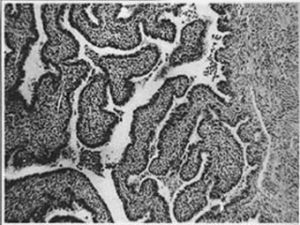

(一)、輸卵管積水及輸卵管卵巢囊腫(Hydrosalpinxandtuboovariancyst):輸卵管積水系輸卵管內膜炎引起傘端閉鎖,管腔中滲出液積聚而成。有的則為輸卵管積膿,部分日久膿液吸收液化,呈漿液狀,演變成輸卵管積水。如原為輸卵管卵巢膿腫則形成輸卵管卵巢囊腫(積水)。此外,有時因卵巢周圍炎使卵泡破裂受阻而形成卵泡囊腫,或卵泡破裂時細菌乘隙而入,形成炎性積液,以後又與輸卵管積水貫通而成輸卵管卵巢囊腫。輸卵管積水常不甚大,均在15cm直徑以下,與輸卵管積膿一樣,呈曲頸瓶狀。輸卵管卵巢積水直徑可達10~20cm左右。兩者都見於炎症多年不復發的病例。外表光滑,管壁因膨脹而菲薄透亮。輸卵管積水一般有纖細膜樣索條與盆腔腹膜粘連,但個別游離。由於遠端膨大較重,偶以近端(峽部)為軸,發生輸卵管積水扭轉,以右側多見。輸卵管積水常為雙側性。其子宮端有時僅疏鬆閉塞,因而作子宮輸卵管碘油造影時,X線透視或攝片可顯示典型的輸卵管積水影象;少數病例訴稱偶有突發性多量或間斷性少量水液自陰道排出,可能為輸卵管積水腔內壓力增大,積液衝出疏鬆閉塞的輸卵管口所致。大量陰道排液後盆腔檢查,可發現原有之包塊消失。